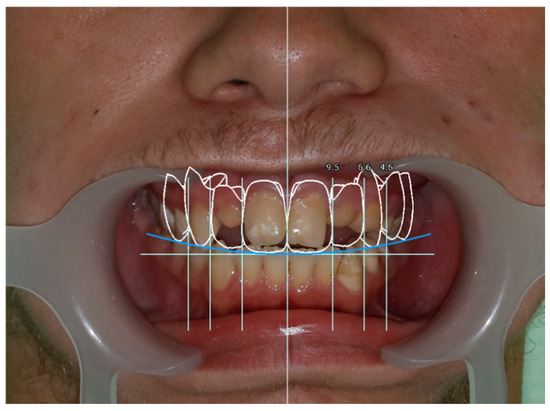

Use of Computer Digital Techniques and Modern Materials in Dental Technology in Restoration: A Caries-Damaged Smile in a Teenage Patient

2. Case Report